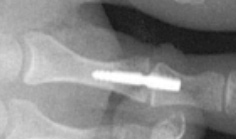

Il s’agit d’une ostéotomie de réaxation courte du 1er métatarsien qui vise à translater la tête de celui ci vers l’extérieur. Le déplacement est fixé par une vis. - Le « Scarf »